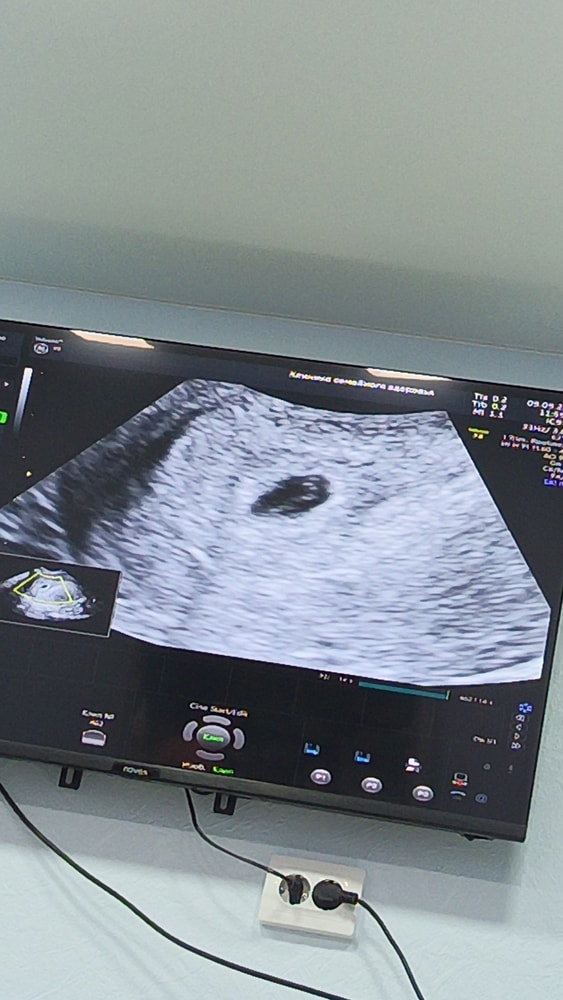

Эмбрион или желточный мешок?

Девочки, снова здравствуйте. Сходила я значит на УЗИ уже платно, прилагаю бумаги.

но вопрос, разве может быть уже и желточный мешок и эмбрион? Или все таки пока просто ЖМ? Но то что кто-то сидит внутри яйца я вижу, самое главное что моя бусинка не пустая)

На втором снимке чётко виден эмбрион с желточным мешком, это уже не просто ЖМ. Сердцебиение должно скоро появиться, если срок подходит. Всё выглядит хорошо.

Ксюша, а сможете объяснить где вы это видите? Я просто поняла черный круг это яйцо, а внутри точка это ЖМ. Исправьте пожалуйста если не так. Срок по узи 5.2, по М-5,5